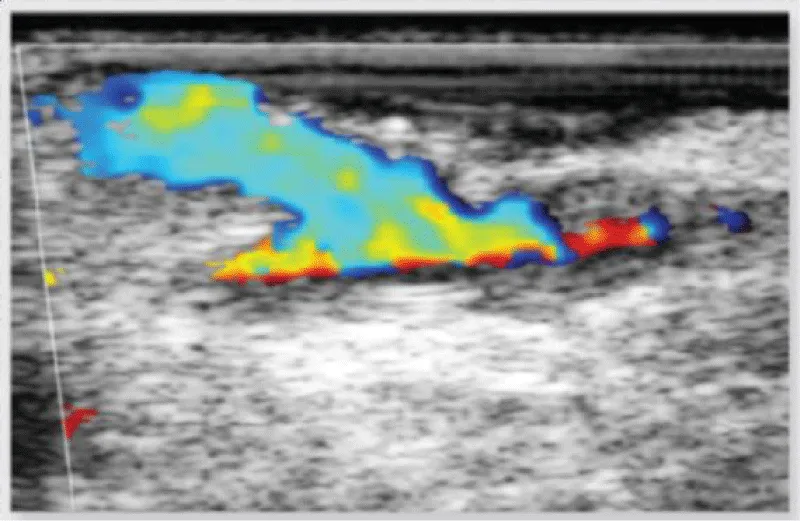

In case of doubt about the quality of the anastomosis (due to technical challenges during the realization of the anastomosis, or obtainment of nonideal PI values), we can assess the result of the anastomosis with the epicardic echography (Figures 12,13):

Figure 12: Echographic evaluation of an anastomosis between the left internal mammary artery and the left anterior descending artery.

Figure 13: Doppler echographic evaluation of an anastomosis between the left internal mammary artery and the left anterior descending artery.